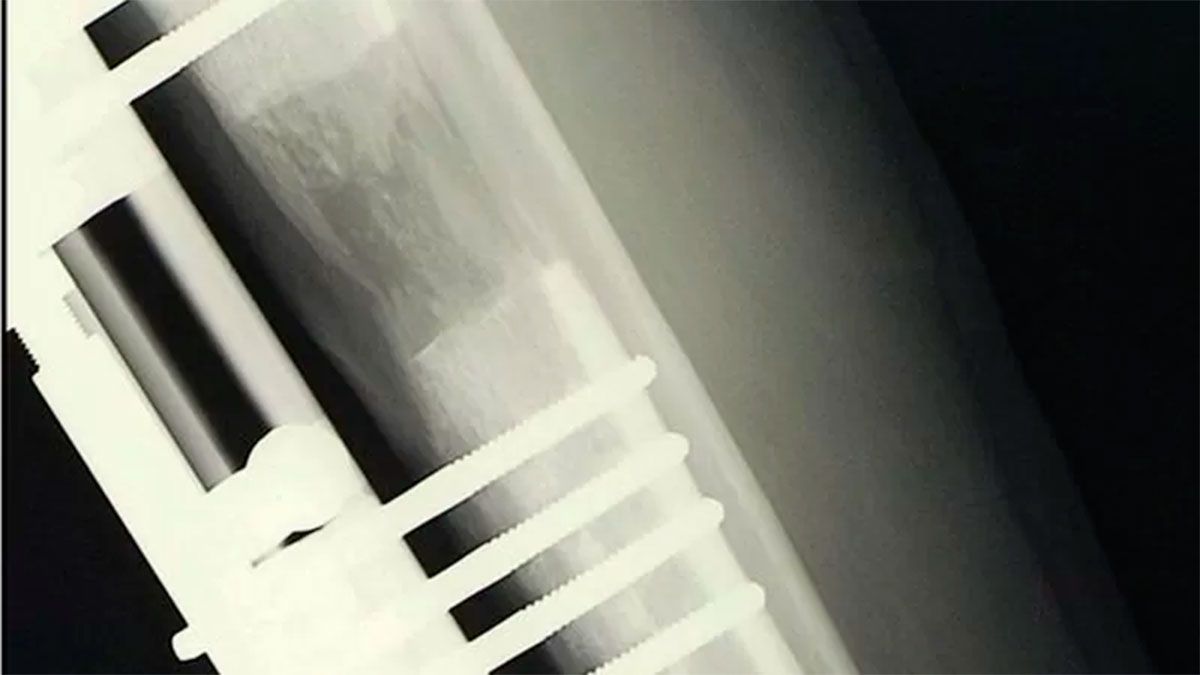

Según explicaron varios cirujanos consultados a BBC Mundo, el tratamiento estándar es el siguiente: primero se perfora y realiza un agujero en los huesos de las piernas, que luego se parten en dos.

Tras esto, se coloca quirúrgicamente una barra de metal en el interior del hueso y se mantiene en su lugar mediante una serie de tornillos.

Luego, la barra se va alargando lentamente hasta 1 milímetro cada día, extendiéndose hasta que el paciente alcanza la altura deseada y sus huesos se dejan hasta que sanen nuevamente.